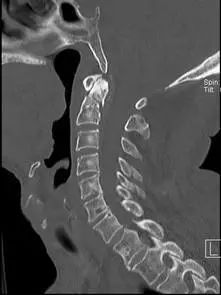

患者,男性,75岁,因外伤致颈部疼痛伴活动受限7天入院。患者入院前在当地医院确诊为:枢椎齿状突骨折Anderson-D’Alonzo分型Ⅱ型。

对于本患者来说,齿状突骨折后导致寰枢椎不稳,极易引起延髓或椎动脉损伤,严重者当场死亡。但患者同时合并严重胸腰椎后凸畸形,颈部后伸受限,不具备前路手术条件,这就给其治疗更增加了额外的困难。而由于手术部位延髓及椎动脉等血管神经密布,手术难度高、风险极大,稍有不慎,患者就会有生命危险。而患者家属在了解到手术的危险性后,曾自行到上级医院咨询专家,上级医院专家考虑围手术期死亡的风险,对于本例患者亦不愿提供手术治疗的机会。

经过全程监护和系统治疗,患者术后恢复良好,骨折解剖复位,复查X线及CT显示固定位置佳,术后3天下地行走,术后4天即出院回家休养。